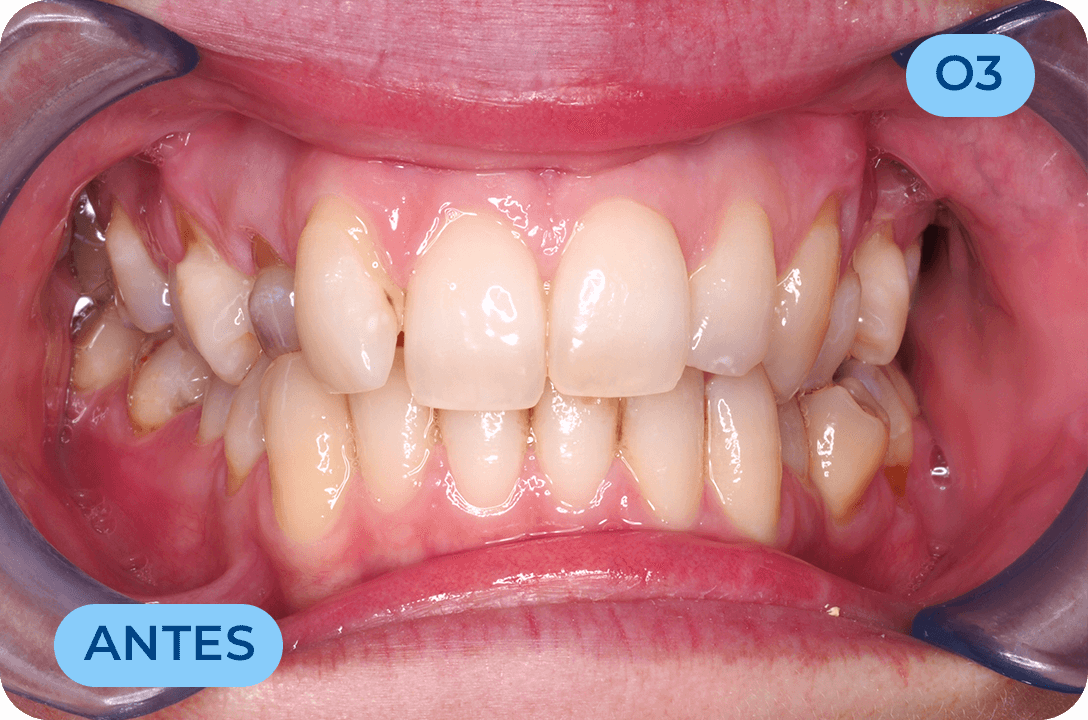

Prostodontia

É a área da Medicina Dentária que atua na substituição de dentes perdidos ou comprometidos esteticamente. Os dentes são substituídos através de dentes fixos (coroas em cerâmica suportadas por implantes ou suportadas por raízes de dentes naturais) bem como próteses removíveis. Mais recentemente surgiram as facetas (lentes de contacto) com a vantagem de conservar mais os tecidos dentários e com ótimos resultados estéticos. É uma área muito importante na reabilitação da função mastigatória assim como da auto estima, recuperando a vontade de sorrir.